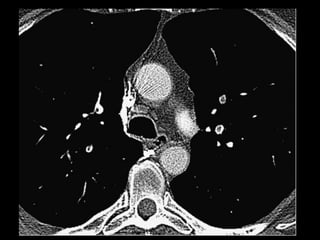

Malformação arteriovenosa(MAV) MAV congênitas: fístulas vasculares com comunicação entre a artéria e a veia pulmonar(95%) ou de uma artéria sistêmica e a veia pulmonar com by-pass do leito capilar; Cerca de 50% das MAVs estão associadas com Síndrome de Rendu-Osler-Weber(teleangiectasia hemorrágica hereditária); O diagnóstico costuma ser bem direto pela TC;

Malformação arteriovenosa(MAV) TC:o aspecto típico é de uma massa regular, lobulada, redonda ou oval, ou até o de uma formação serpenginosa, com menos de 1 cm a vários cm de tamanho, associada a uma artéria nutriz visivelmente aumentada e uma veia de drenagem alargada; Uma ANGIO-TC geralmente faz o diagnóstico; Tratamento pode ser realizado com terapia embólica.